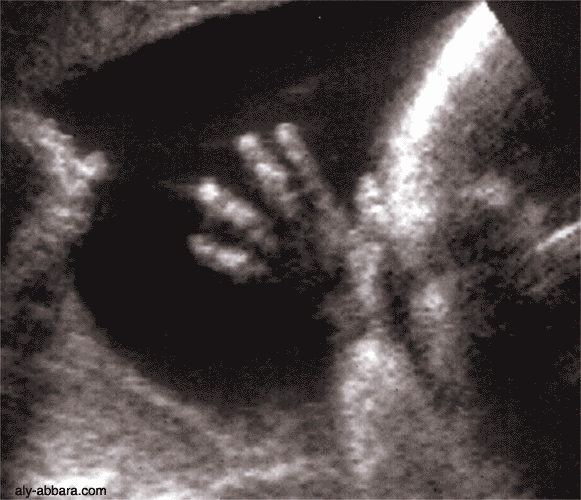

Coupe échographique montrant les détails d'une main d'un fœtus à 29 SA

Il ne faut pas croire qu'il est possible de visualiser, à chaque échographie, les mains fœtales avec aussi de détalles, car cette

image a été réalisée avec un temps d'acquisition de quelques fractions de seconde avec un mémoire rétrograde à l'appuie

donc cette image est une histoire de chasse